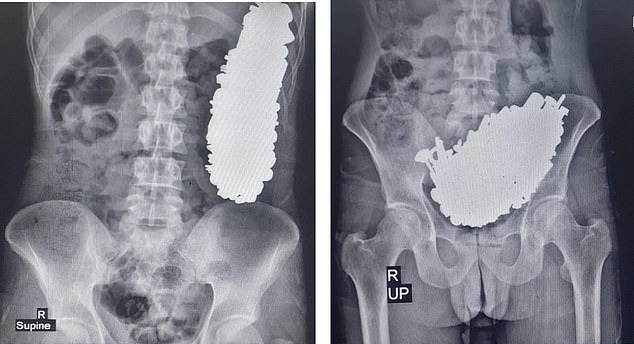

據英國《每日郵報》報導,這名男子因有慢性腹痛、經常嘔吐,且無法正常進食而就醫,但醫師照了X光後驚見,男子的胃部塞滿非食物的物體。隨後醫師為他進行手術,從他胃出取出多達452件金屬零件,包括螺絲、螺帽、鑰匙、徽章、石頭等物品,而且總共重達約3公斤。醫師也研判,男子至少在過去這3個月內,狂吞這些金屬製品。

醫師檢查男子胃部,都被金屬製品塞滿。(翻自《每日郵報》)

醫師從男子胃部取出452件金屬製品。(翻自《每日郵報》)